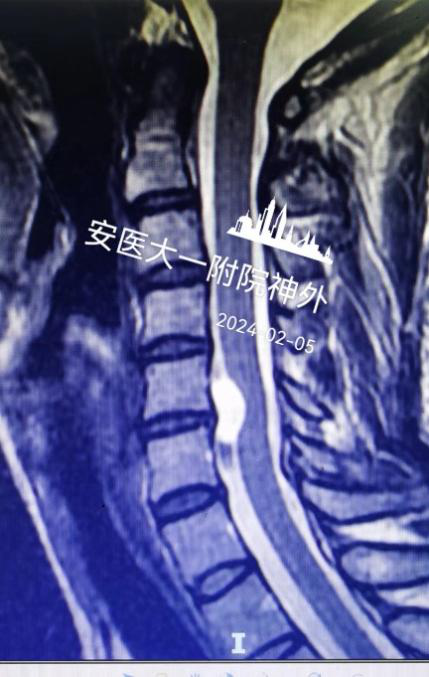

该患者系“右上肢麻木伴左下肢疼痛半年”入院,术前颈椎MR提示C5-6水平脊髓前方囊性占位(图1),囊肿的基底部位于前正中裂至中央管内(图2)。经科室讨论,采用显微镜下颈前经椎体入路脊髓内肠源性囊肿切除术。术后第四天复查磁共振见囊肿全切,无残留(图3),术后颈椎X线片显示内固定位置良好,颈椎曲度理想(图4.5)。术后患者恢复良好,术后第四天患者自己可以下床行走,四肢肌力正常(图6),右上肢麻木稍减退,左下肢疼痛感消失。

图3:术后第4天复查肿瘤没有残留